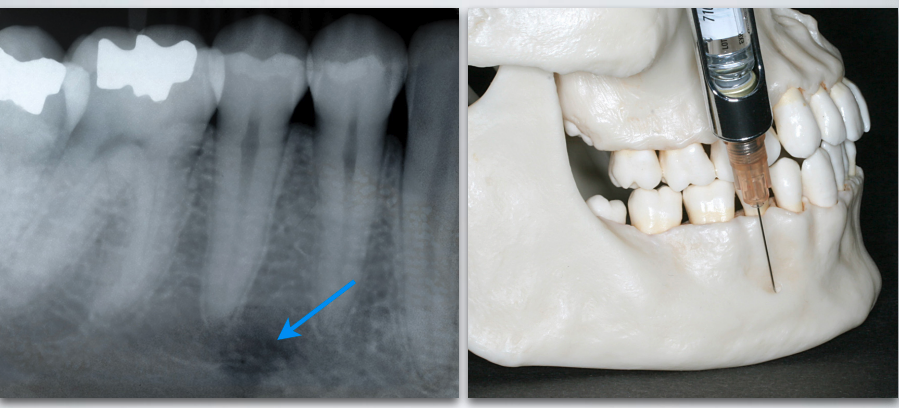

when doing MENTAL/INCISIVE NERVE BLOCK, locate the mental foramen with the aid of…?

radiographs and gentle palpation

what nerve is indicated here?

mental/incisive nerve

what is the proper target site for MENTAL/INCISIVE NERVE BLOCK?

Mental nerve as it exits mental foramen (between apices of the 1st and 2nd premolar)